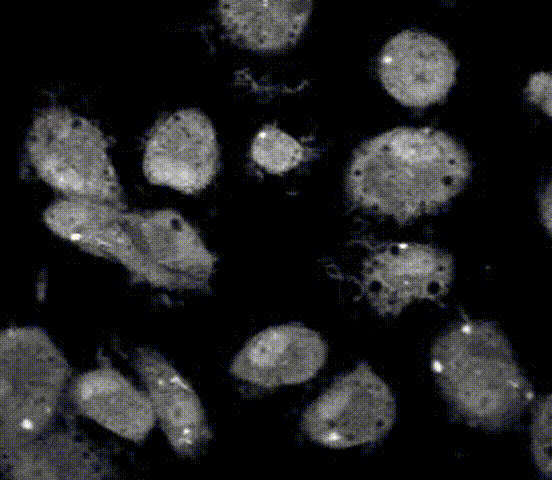

事实上,细菌进入细胞之后,被感染的细胞还会出现一个非常惊人的现象。这是我们用DNA染料对细胞进行染色后拍摄的动图。正常情况下,由于细胞膜存在严格的过滤系统,这个染料是无法进入细胞内的。但我们观察到,当细胞被胞内菌感染时,这个染料就能够进入细胞了,细胞变红了,而且整个细胞核红得发亮。为什么这时染料能进去呢?因为胞内细菌的感染使细胞膜的通透性发生了变化,细胞膜发生了破裂。这种裂解性的细胞死亡过程就是细胞焦亡的直观体现。

我们人为的把5个GSDM“小炸弹”一个一个放到这个细胞里面去试验,发现当Gasdermin B (GSDMB)放进去时,让NK细胞去攻击它后,我们看到靶细胞里面的绿色荧光染料消失了,而添加在培养基中的红色核酸染料,也就是细胞外部的染料,进入了细胞内部。这就表明细胞膜出问题了。里面的绿色物质被释放出来,外面的红色染料进去把DNA染上了红色。这是细胞发生了焦亡。